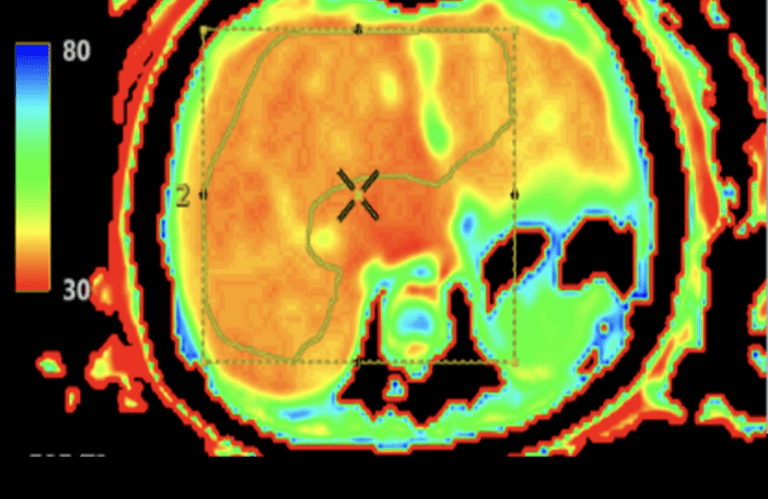

Det är en stor studie där barnen genomgår flera olika undersökningar under tre dagar. Det handlar bland annat om arbetsprov med gasanalys, hjärtultraljud, lungfunktionsundersökningar, MR av hjärta och lever, samt undersökningar av lymfsystem och blodkärl.

En annan viktig observation är att MR av hjärtat verkar ge den mest tillförlitliga bilden av hjärtfunktionen vid enkammarcirkulation. Forskarna har också sett att ökad stelhet i levern hänger ihop med förändringar i lungblodflödet.